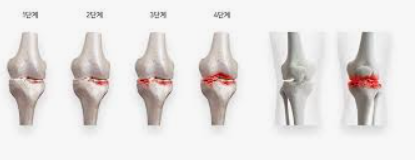

증상은 점진적으로 발전하며, 초기에는 운동 후 통증이 나타나기 시작합니다. 시간이 지남에 따라 휴식을 취해도 통증이 지속되며, 관절의 경직과 부기가 동반됩니다. 심한 경우에는 관절의 변형까지 발생할 수 있습니다. 날씨가 추울 때나 습할 때 통증이 더 심해지는 것을 경험할 수도 있습니다.

퇴행성 관절염, 일명 '골관절염'은 관절을 보호하는 연골이 닳아 없어지면서 발생하는 질환입니다. 이는 관절의 통증, 부기, 그리고 운동 범위의 제한을 초래할 수 있습니다. 퇴행성 관절염의 원인은 다양하며, 여러 요소가 복합적으로 작용합니다.